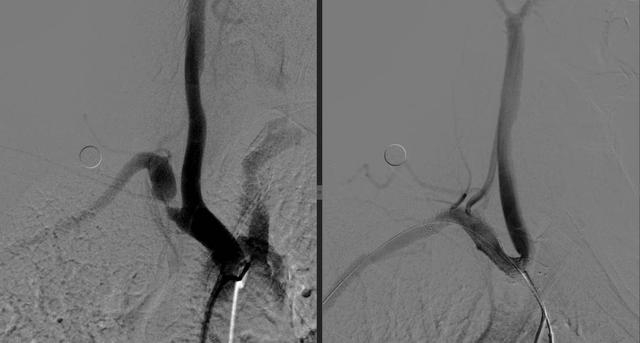

术前术后对比,术后锁骨下动脉盗血消失

“简单来说,就是有根血管有问题,导致供应大脑的血液有的时候被‘盗走了’,发病的时候就出现了类似中风的表现。”文主任解释,患者一侧的锁骨动脉狭窄,另一侧正常,所以测量两只胳膊的血压时会出现一个高、一个正常的情况。明确病因后,文立利为其进行了介入手术治疗,在动脉狭窄处进行球囊扩张并置入支架。术后王大爷头晕的情况随即消失,血压也恢复正常。